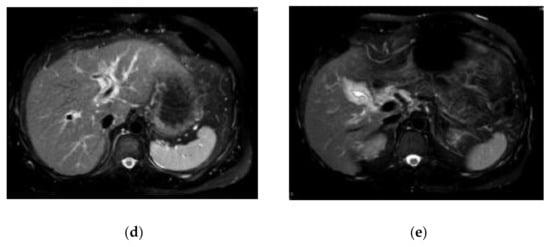

The laboratory data on admission are listed in Table 1. Liver dysfunction was observed in addition to severe transaminase levels. Hepatitis viral markers and autoantibodies were negative. Thyroid function was within normal limits: thyroid stimulating hormone, 1.66 μIU/mL; free tri-iodothyronine, 3.25 pg/mL; and free thyroxine, 1.49 ng/dL. We also performed a drug lymphocyte stimulation test (DLST). DLST was positive for benzbromarone (stimulation index (SI), 561%), Hyakusosan (SI, 406%), and bilastine (SI, 403%). These drugs were provided by this patient. On the DLST, the drug at 0.1, 1 or 10-fold of maximum plasma concentration was added to the lymphocytes separated from our patient’s plasma. Lymphocytes were cultured for 72 h, and 3H-thymidine was then added [14]. After culturing the lymphocytes for 16–18 h, radioactivity resulting from the uptake of 3H-thymidine was measured by the cells during deoxyribonucleic acid (DNA) synthesis in counts per minutes (cpm). The SI was calculated as the ratio of proliferation (cpm) with the drug/proliferation (cpm) without the drug [14]. Abdominal ultrasound, computed tomography and magnetic resonance imaging results indicated acute liver injury (Figure 1). We did not observe any signatures of chronic hepatitis or cirrhosis.

Figure 1.

Findings of abdominal ultrasound (US) (a), computed tomography (CT) (b,c) and magnetic resonance imaging (MRI) (d,e) examinations. US indicated acute liver injury with thickening of the gall bladder wall and minimal ascites on the underside of the liver (a). The contrast-enhanced CT scan also indicated acute liver injury with thickening of the gall bladder wall (b,c). MRI indicated acute liver injury with periportal abnormal intensity (d) and thickening of the gall bladder wall (e).